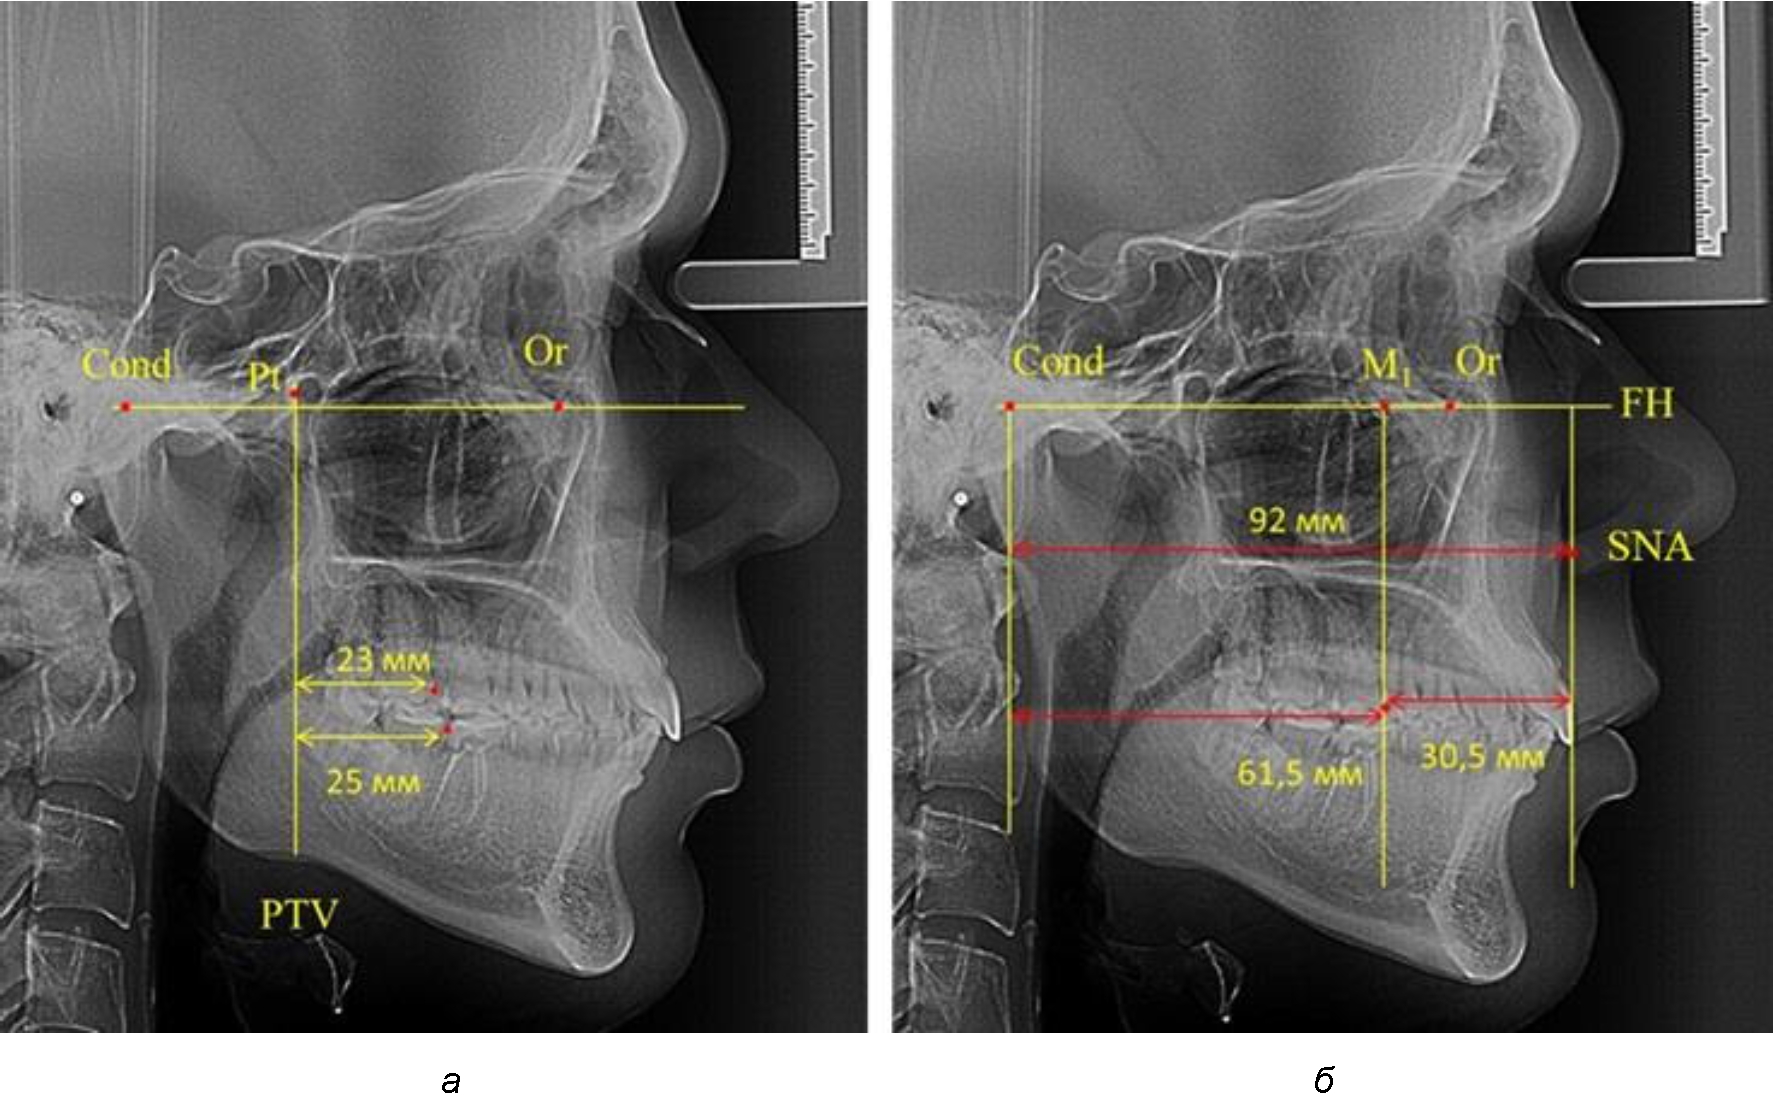

В то же время при увеличенном расстоянии от крыловидной вертикальной плоскости PTV до дистальной поверхности верхнего первого постоянного моляра, равное 23 мм, сагиттальный размер гнатического отдела составил 92 мм. При этом отношение кондилярно-спинального расстояния к кондилярно-молярному размеру (30,5), так же, как и при малых размерах, было близким к коэффициенту 1,5, что представлено на рис. 3.

Рис. 3. Особенности положения первых моляров по R. E. McDonald (а) и по предложенному методу (б) при увеличенном молярно-крыловидном расстоянии